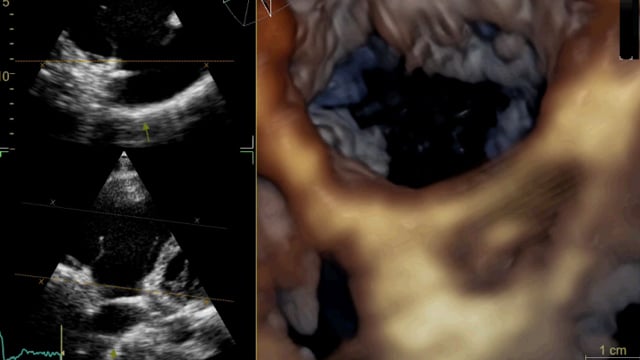

Tricuspid valve - How to evaluate?

12 Sep 2025 – From PCR Rio Valves 2025

This session offers a detailed evaluation framework for the tricuspid valve, encompassing clinical decision-making, anatomical assessment with 2D and 3D imaging, quantification of regurgitation, and differentiation of secondary and device-related tricuspid regurgitation, supported by advanced imaging software techniques.